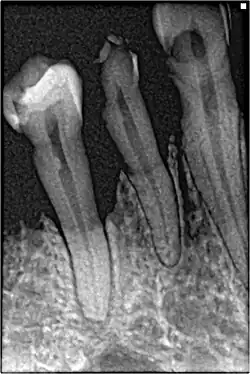

Cáncer de pulmón

Algunos tipos de cáncer se encuentran directamente relacionados con el tabaco, como es el caso del cáncer de pulmón y otros cánceres del tracto respiratorio. Esto se debe al contacto directo que presentan las células de estos tejidos con los componentes químicos presentes en el tabaco y que son perjudiciales para la salud. Sin embargo, existen otros tipos de cáncer en tejidos en los que la exposición al tabaco no es de manera directa, en este caso el desarrollo tumoral ha sido atribuido a procesos inflamatorios por depósito de partículas.[18]

La contribución del tabaco a la aparición de cáncer se debe a la gran mezcla de compuestos químicos que se encuentran tanto en el humo como en el tabaco que aún no ha sido quemado. Únicamente analizando los componentes del humo, se han llegado a encontrar hasta 70 carcinógenos, de entre los cuales pueden destacarse 3 grupos de compuestos:[18]

Desde el punto de vista biológico, estos carcinógenos son activados por el citocromo P450, el cual, y bajo circunstancias fisiológicas, produciría su metabolismo para posterior excreción. Sin embargo, ante acumulación de estos agentes de naturaleza química, la activación por parte del citocromo P450 permite que estos carcinógenos puedan interactuar con el ADN debido a su naturaleza electrofílica y afinidad de unión al ADN. De esta interacción entre los compuestos del tabaco y las bases nitrogenadas del material genético aparece la formación de aductos de ADN. Estos son uniones de los productos químicos al ADN que provoca daño e impiden la correcta y completa repliación del material genético, aumentando así la probabilidad de que aparezcan nuevas mutaciones, que lleven al desarrollo de cáncer.

En circunstancias fisiológicas normales los sistemas de reparación del ADN se encargan de reparar estas estructuras y eliminarlas, pero si persisten a esta reparación y además se disponen en regiones donde se encuentran oncogenes tales como Myc y Ras o bien en regiones de genes supresores de tumores como P53. Esto provoca una pérdida de control sobre el crecimiento celular, lo cual será la fase inicial de la formación de tumores.